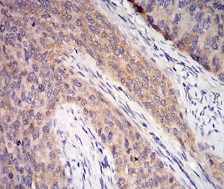

IHC    1/200 - 1/1000